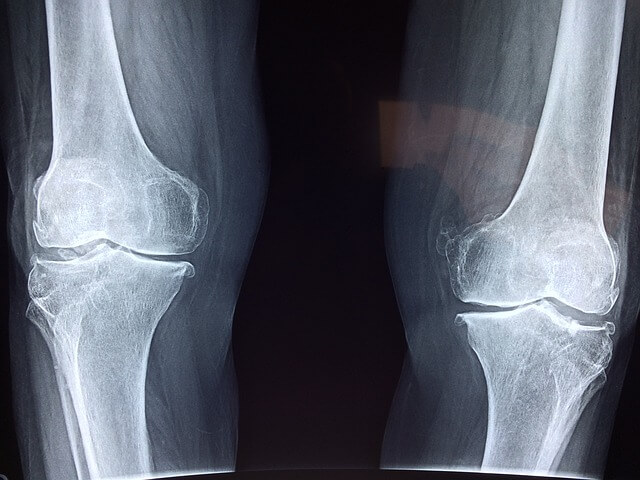

3) 무릎 연골은 무릎의 위쪽 뼈와 아래쪽 뼈의 충격이나 마찰을 줄여주는 역할을 합니다. 그런데 연골이 손상되어 닳아 없어지면서 무릎을 구부릴 때 뼈와 뼈가 서로 맞붙으면서 통증을 일으킵니다

무릎은 인체의 복잡하고 중요한 관절로, 신체의 무게를 지탱하고 균형을 유지하는 중추적인 역할을 합니다. 근육과 체중에 의해 생긴 힘을 허벅지에서 하체와 발로 전달하는 역할을 합니다

무릎의 역할은 다리를 구부리고 펴는 것을 가능하게 합니다. 걷기, 달리기, 쪼그려 앉기, 오르기와 같은 활동 과정에서 몸을 앞으로 나아가게 하고 균형을 유지하도록 돕습니다. 그리고 점프나 착지와 같은 활동을 할 때 발생하는 충격을 분산시키고 흡수하는 역할도 합니다